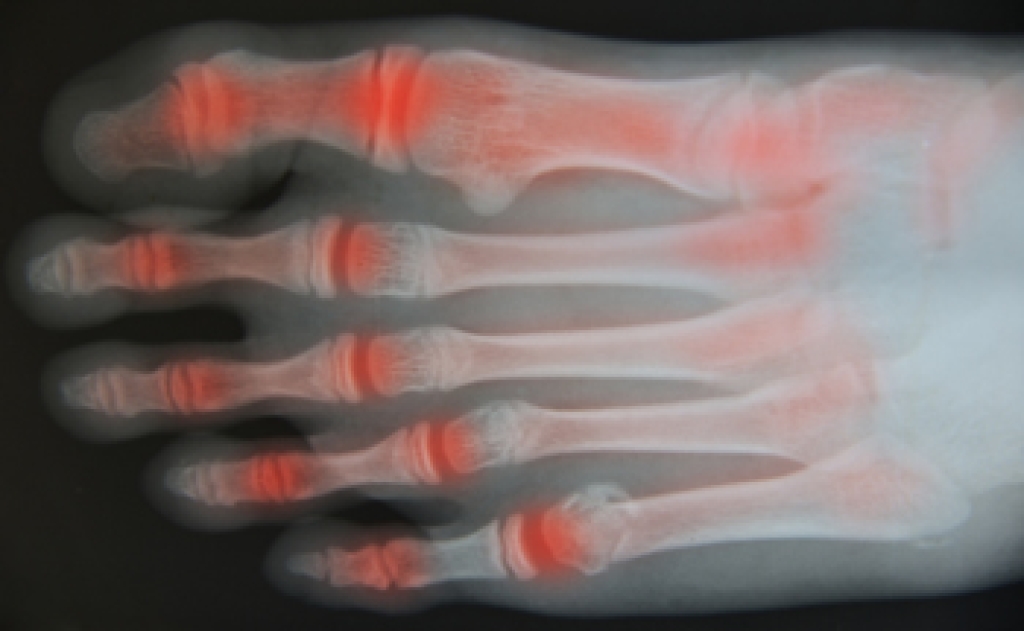

Rheumatoid Arthritis (RA) is an autoimmune disorder in which the body’s own immune system attacks the membranes surrounding the joints. Inflammation of the lining and eventually the destruction of the joint’s cartilage and bone occur, causing severe pain and immobility.

Rheumatoid Arthritis of the Feet

Although RA usually attacks multiple bones and joints throughout the entire body, almost 90 percent of cases result in pain in the foot or ankle area.